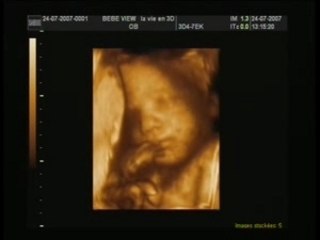

Orlane et leau